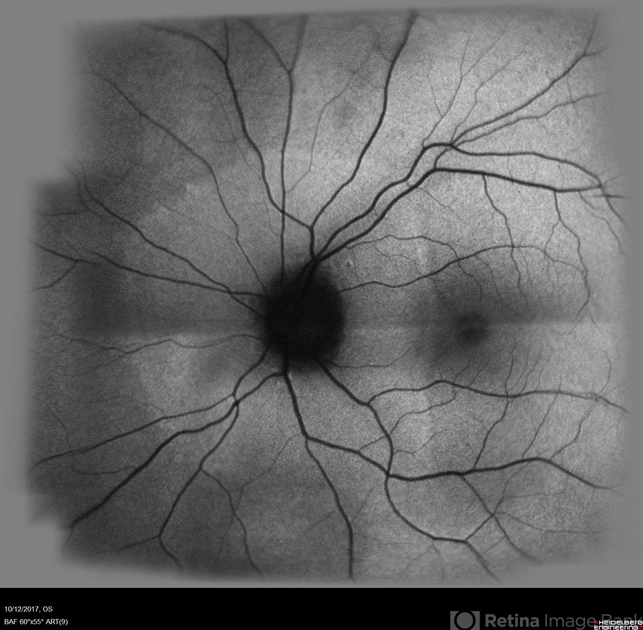

- acute zonal occult outer retinopathy (AZOOR)

- Fundus autofluorescence OS showing peripapillary hypoautofluorescence surrounded by an area of hyperautofluorescence with well demarcated margins suggestive of AZOOR.